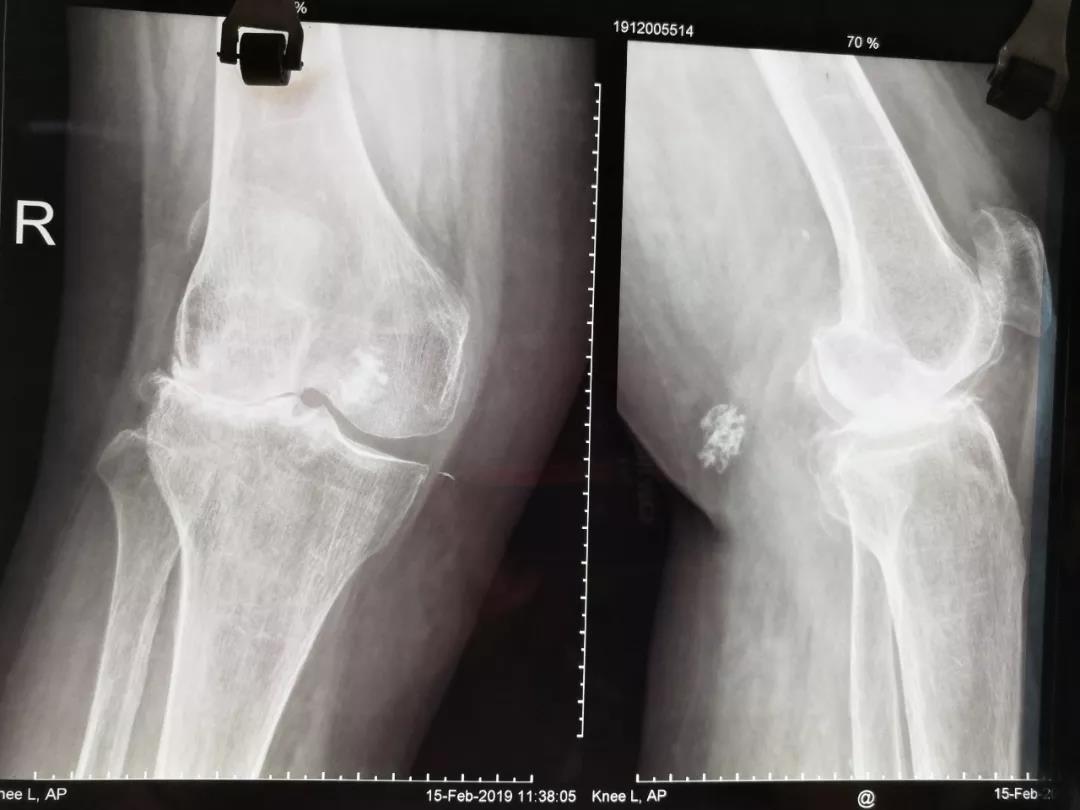

近日,焦作市人民医院关节外科施行一例“严重膝关节外翻人工关节置换术”,解除了患者长达六年的痛苦。         患者孟XX,六年前感右膝关节 ...